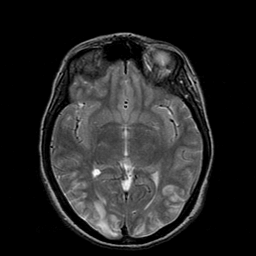

Hypertensive Encephalopathy, overlay -- Slice #11

[Home][Help][Clinical] Slice 11